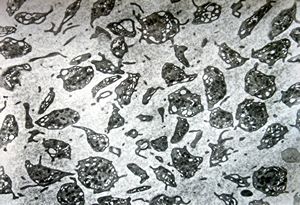

bone marrow - crystalloid inclusions Charcot-Leyden crystals formation

bone marrow - crystalloid inclusions Charcot-Leyden crystals formation v.s.